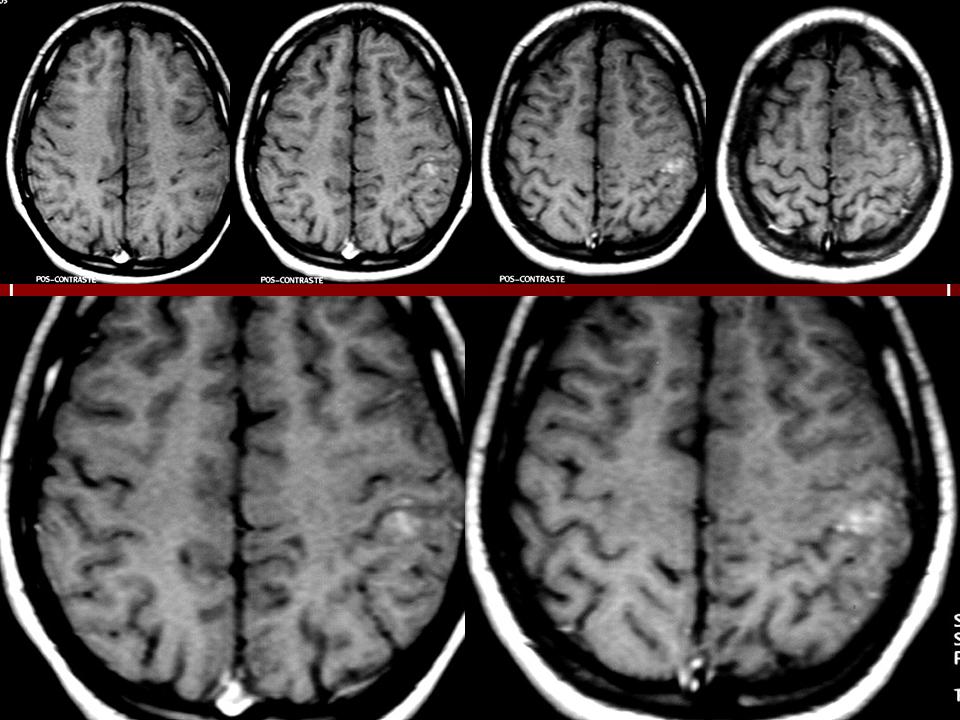

ГМ. Миксоидная саркома. +

Миксоидная саркома.